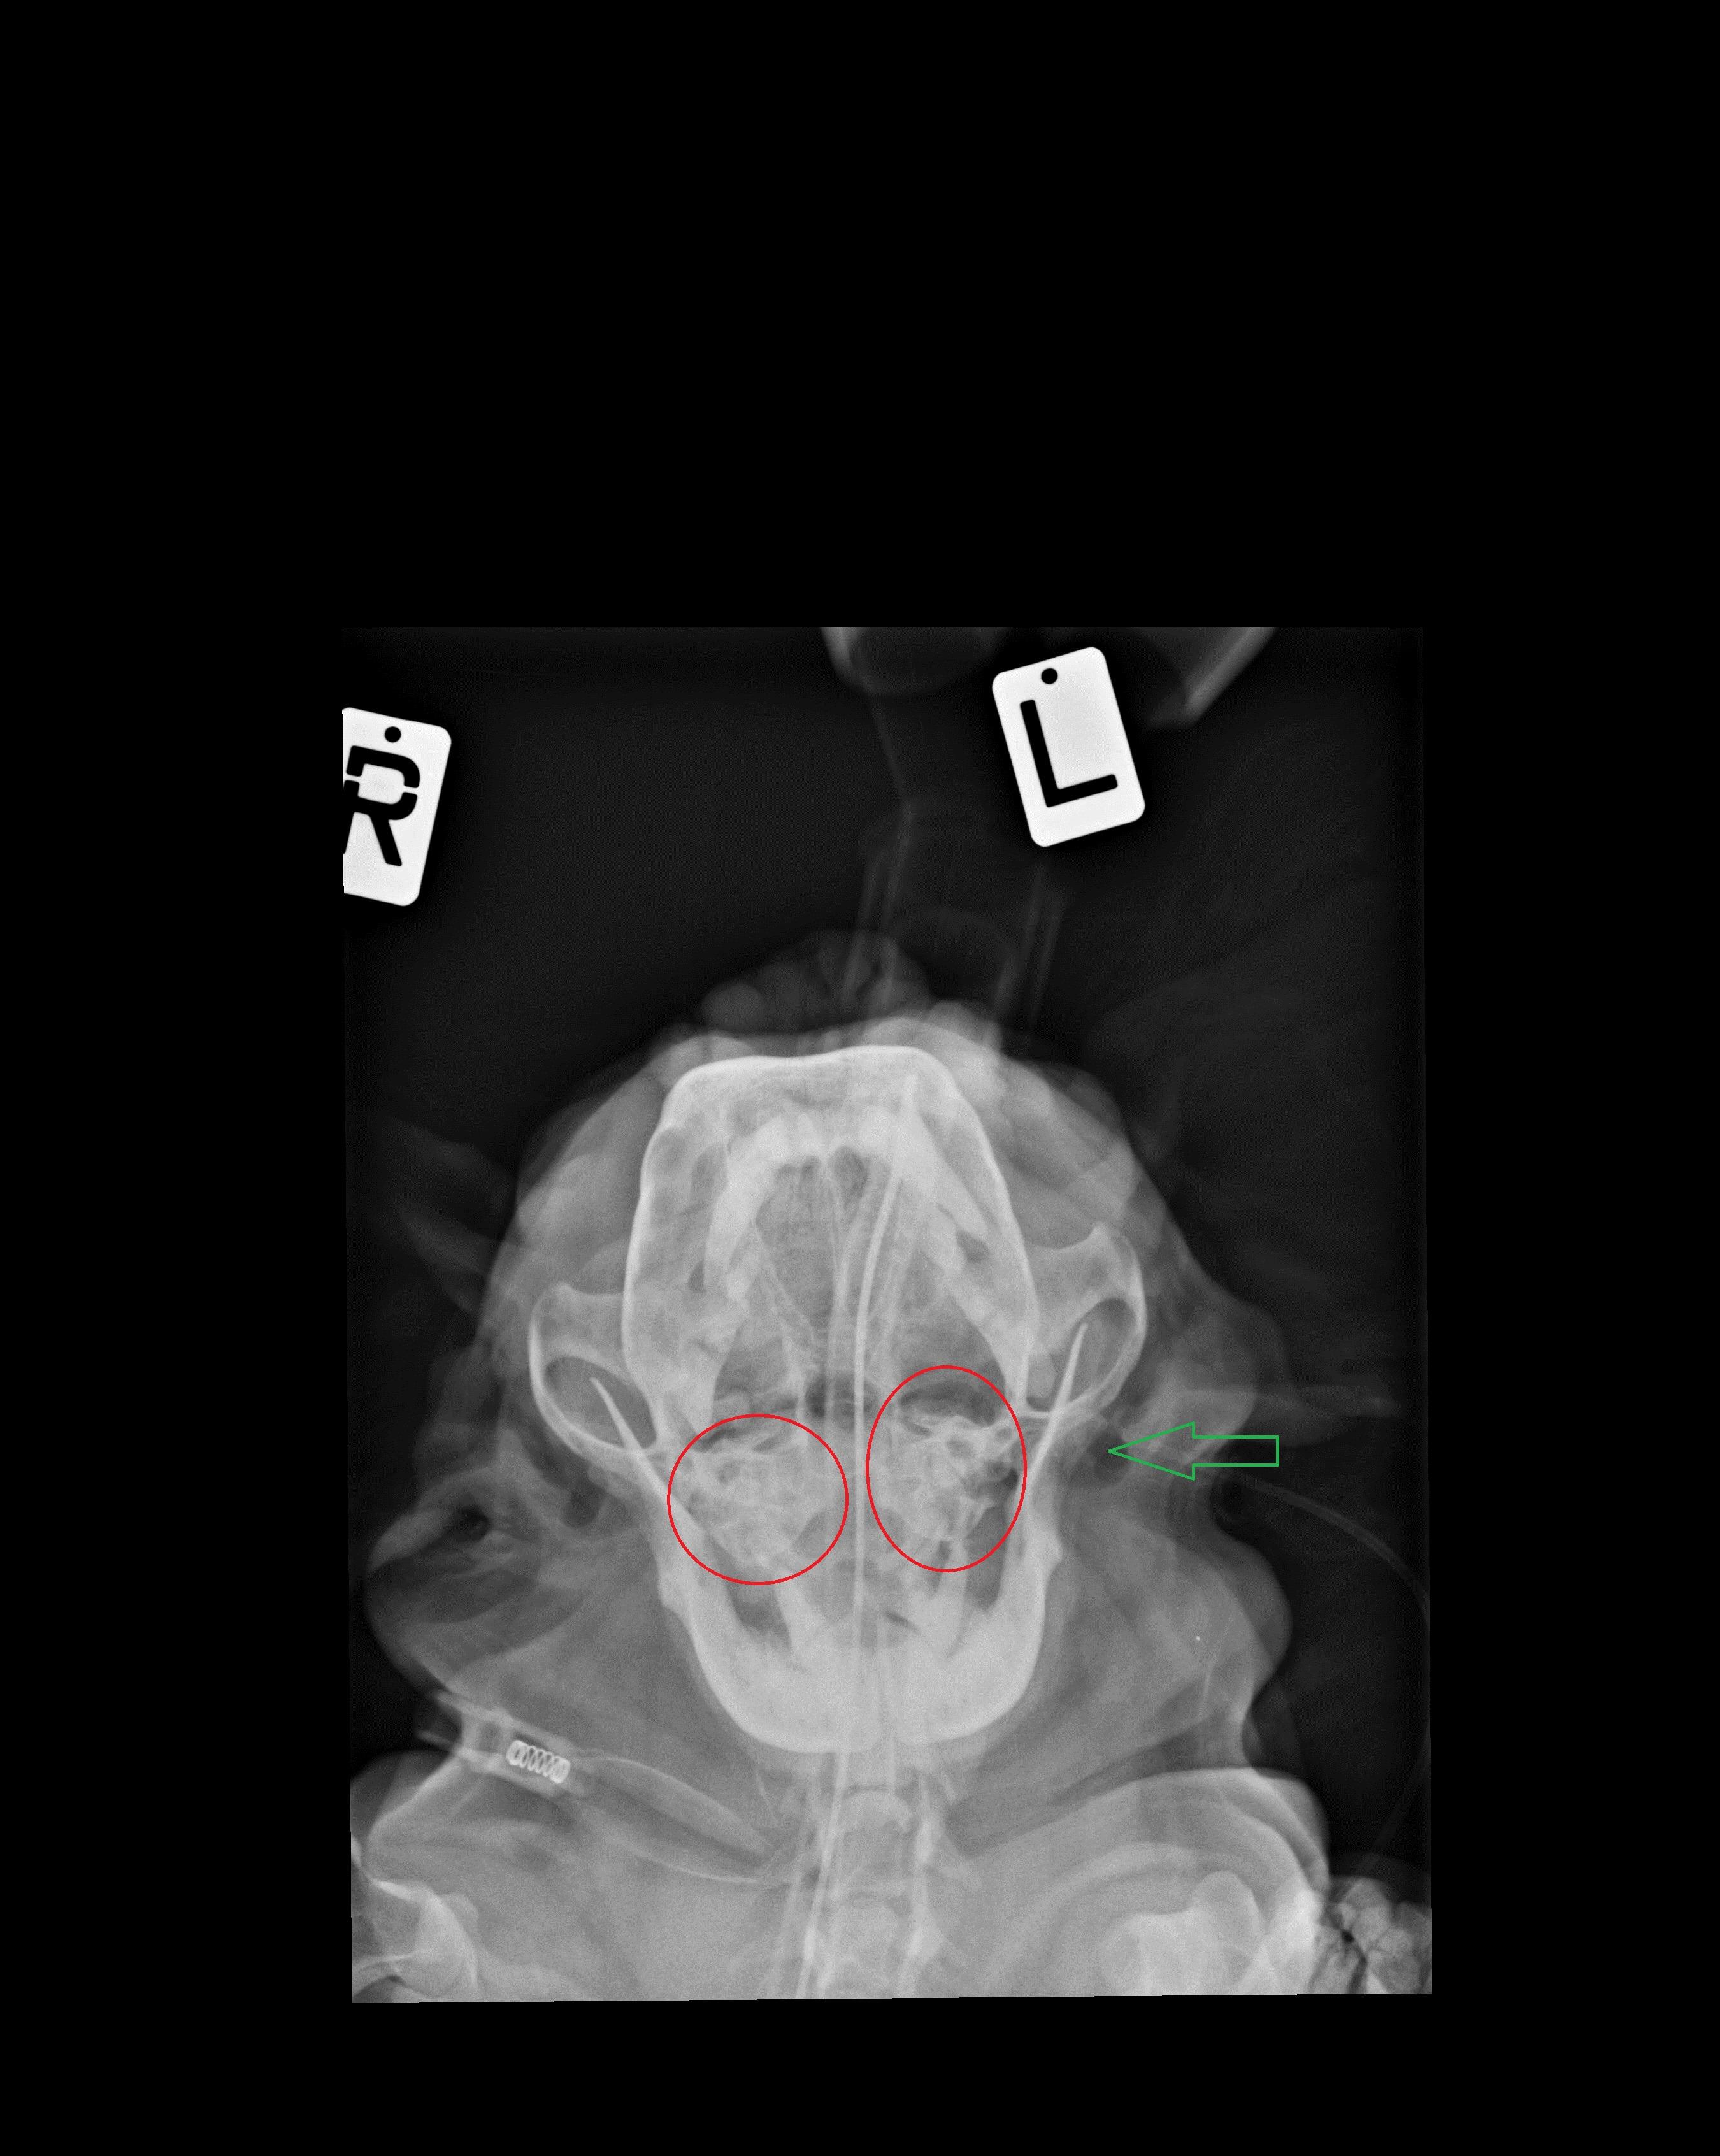

My dog (Cavalier) is showing signs of loss of hearing. She can no longer hear me when I call her from a distance. My vet has diagnosed "glue ear" and recommending myringotomy in both ears. Is this necessary or even advisable?

This is unfortunately not uncommon in Cavaliers and yes a myringotomy is an appropriate treatment. You could pursue more advanced imaging (a CT or MRI) before surgery to get more comfortable that it's required in Layla's particular case. Here is some more general info about "glue ear" https://www.vetinfo.com/glue-ear-in-dogs.html